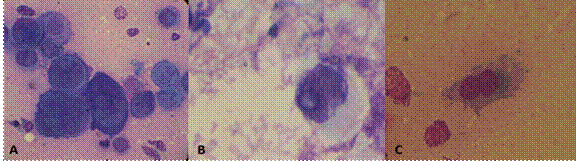

Figura 2. Test de Tzanck realizado en frotis de sedimento urinario de pacientes seropositivos para infección por HHV-6.

reus-23-64002.gif

Se observan células gigantes binucleadas y multinucleadas, núcleos con cambios megaloblásticos y cromatinas desplazadas. A. Caso 2, B. Caso 4, C. Caso 6 (imágenes observadas a 100X), diagnóstico realizado en el Laboratorio de Inmunología de la Universidad del Cauca. Fuente: propia del autor.

En cuanto al test de Tzanck, los pacientes 2, 4 y 6 mostraron cambios morfológico intranucleares e intracitoplasmáticos como células gigantes multinucleadas, que forman sincitios en forma de globo, núcleos megaloblásticos e inclusiones intranucleares e intracitoplasmáticas por virus, lo que confirma actividad viral, y se ha descrito específicamente para HHV-612. Sin embargo, esta técnica tiene una baja sensibilidad (60-70%)13, lo que se considera una técnica complementario al diagnóstico de la familia herpesviridae14.